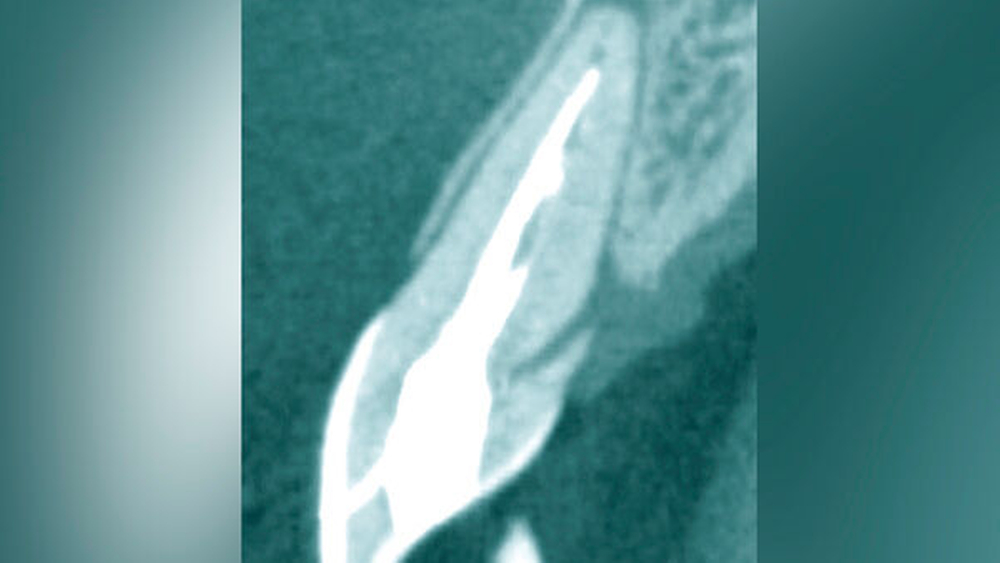

Eine weitere Möglichkeit, tief zerstörte Zähne möglichst schonend chirurgisch zu extrudieren, basiert auf axialen Zugsystemen (Abbildungen 2 bis 4). Diese erscheinen vorteilhaft bei sehr schwierigen Fällen, zum Beispiel bei Zähnen mit fehlendem Ansatzpunkt für die Zange sowie bei langen oder sehr ovalen Wurzeln. Axiale Zugsysteme ermöglichen die Übertragung von Zugkräften auf die Zahnwurzel, ohne die Alveole unnötig zu dehnen. Dazu wird eine spezielle Schraube in den Wurzelkanal eingebracht und das Gewinde der Schraube für eine ausreichende Friktion fingerfest eingedreht. An diese Schraube wird ein gerätespezifisches Zugsystem angelegt. Durch rein axial wirkende Zugkräfte werden traumatische Effekte auf Knochen und Wurzeloberfläche während der Zahnmobilisation minimiert. Gegebenenfalls können feine Luxatoren vorsichtig unterstützend eingesetzt werden. Im Tiermodell wurde an extrahierten und wieder replantierten Zähnen mit ovalem Querschnitt gezeigt, dass der Verlust von Zementoblasten auf der Wurzeloberfläche geringer ist, wenn ein axiales Zugsystem anstatt einer Extraktionszange verwendet wird.

Die wesentliche technische Komplikation stellt das unverhältnismäßige Erweitern des Wurzelkanals für die Retention des Zughilfsmittels – zum Beispiel der Benex-Schraube – dar. Der Behandler sollte hier unter besonderer Vorsicht den bereits instrumentierten und präparierten (vorgegebenen) Wurzelkanal als Bohr- und Zugpfad für die Extrusion nutzen. Auf die Schonung der gesunden Zahnhartsubstanz muss geachtet werden. Die Bohrachse für die Ausrichtung der Zugschraube muss mit dem koronal gelegenen Hauptpfad des Wurzelkanals übereinstimmen. Zudem ist für das Erzielen einer ausreichenden Retention der Schraube ein gewisses Maß an Feingefühl und Taktilität vom Behandler erforderlich. Eine neue Schraube erfüllt die Vorbedingung eines schneidfreudigen Gewindes und damit eines guten Halts im Zahn am besten.